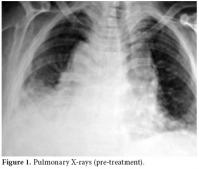

The RA disease activity score (DAS) was calculated as 6.14. Predominant findings in hand X-rays were symmetric joint erosions in carpal bones along with ankylosis leading to contracture, joint space narrowing, cystic changes, and periarticular osteoporosis (figure 5).